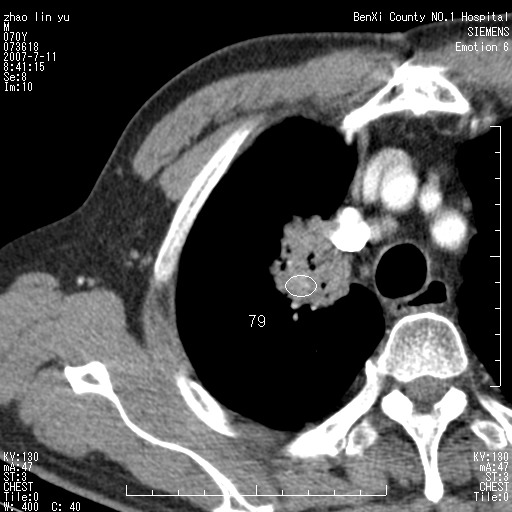

以下是引用王靖旗在2007-7-10 17:12:00的发言:[br] 男、70、咳嗽两个月,半年前换瓣手术,胸片未见异常,于昨天行x片发现右肺上野大片影,行ct扫描,这里是减薄图像,余肺正常。明天晚上会有增强扫描片,到时我会上传。[br][br] 冠状位请大家细看,应该是有意义的,[br][br] 请大家先看平扫发表意见。[br][br]

以下是引用zhangzhongshou在2007-7-10 21:43:00的发言:[br]右肺上叶周围型肺癌,以孤立型细支气管肺泡癌可能性大。